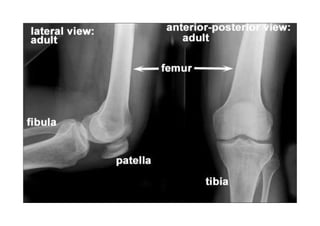

Referência: http://www.accessexcellence.org/RC/VL/

figura